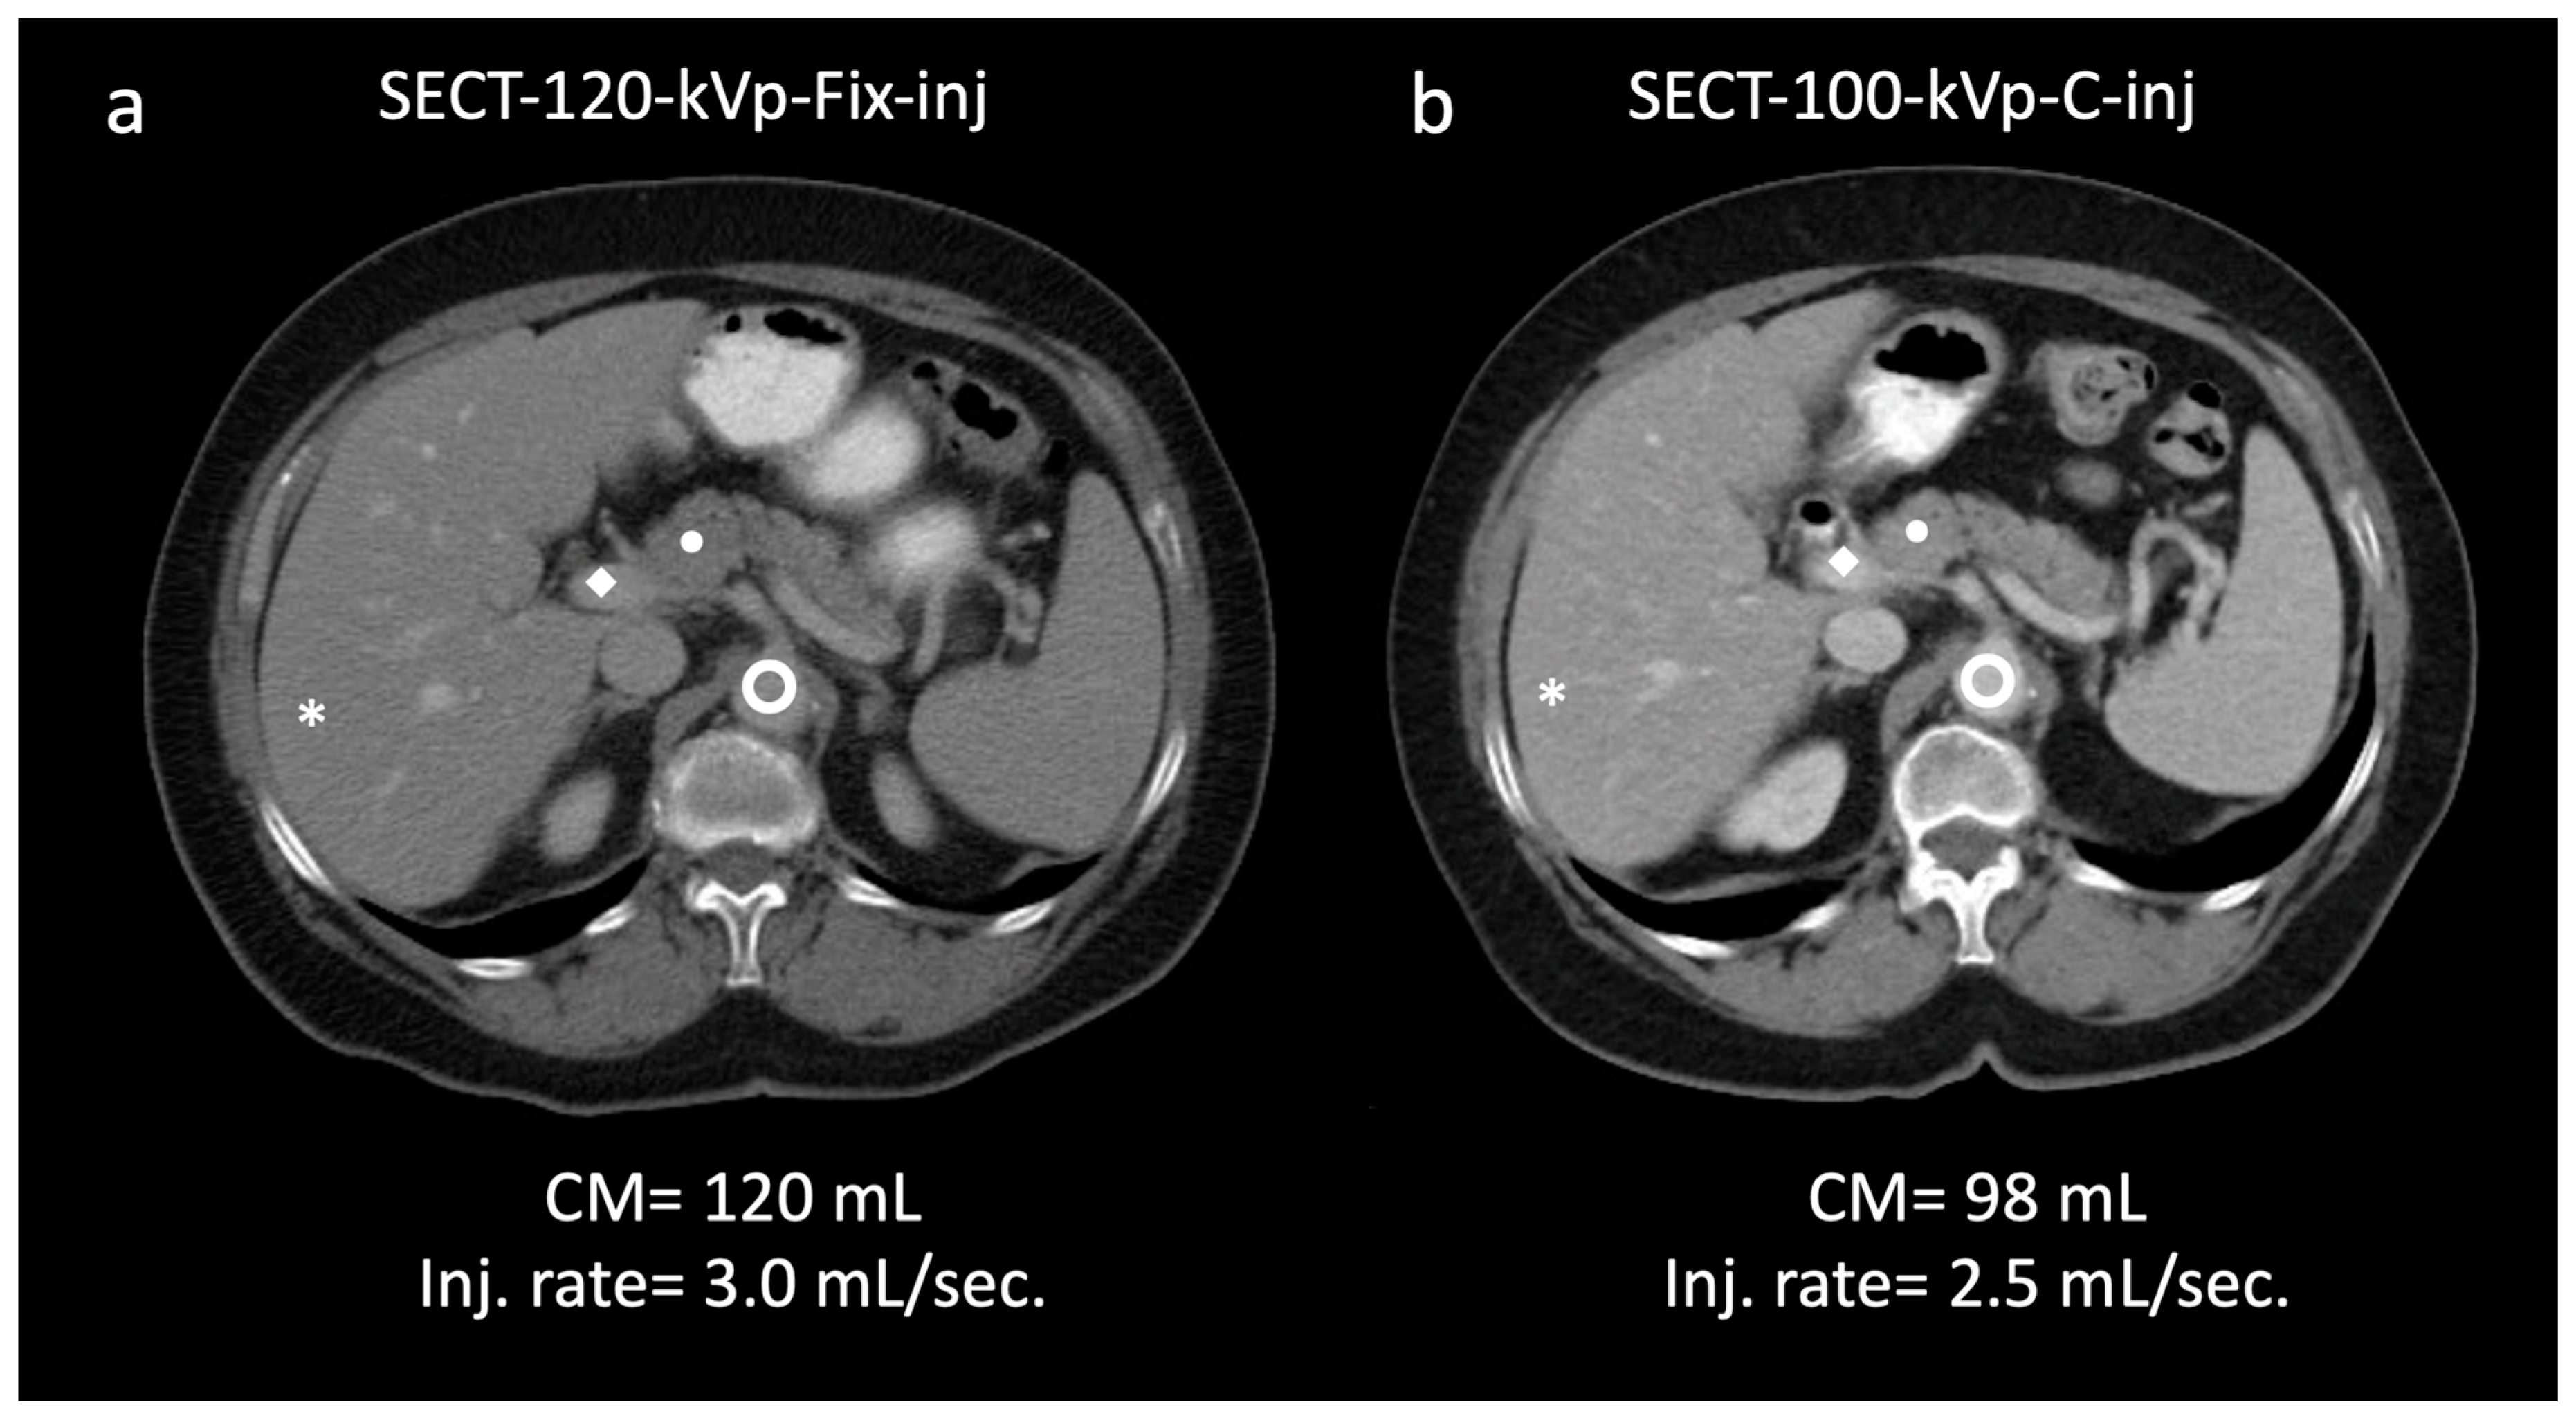

aorta; 145.9/22.8; ◆ portal vein; 157.9/24.7 (a). In the same patient, a 100 kVp SECT with customized injection resulted in administration of reduced volume of contrast media and injection rate (98 mL; −15%; 2.5 mL/s; −16.6%, respectively) and yielded significantly higher attenuation/CNR values: * liver; 106.2/26.7 (+8.8/36.2%); ● pancreas; 93.1/22.2 (+11.0/32.9%);

aorta; 145.9/22.8; ◆ portal vein; 157.9/24.7 (a). In the same patient, a 100 kVp SECT with customized injection resulted in administration of reduced volume of contrast media and injection rate (98 mL; −15%; 2.5 mL/s; −16.6%, respectively) and yielded significantly higher attenuation/CNR values: * liver; 106.2/26.7 (+8.8/36.2%); ● pancreas; 93.1/22.2 (+11.0/32.9%);  aorta, 167.0/30.6 (+14.4/34.2%); ◆ portal vein, 188.8/32.5 (+19.5/31.5%) (b). Subjectively, both readers rated the two scans as 5. Note—Fix-inj, fixed injection; C-inj, customized injection. SECT-100 kVp-C-inj: single-energy CT at 100 kVp with customized injections; SECT-120 kVp-Fix-inj: single-energy CT at 120 kVp with fixed injections.

aorta, 167.0/30.6 (+14.4/34.2%); ◆ portal vein, 188.8/32.5 (+19.5/31.5%) (b). Subjectively, both readers rated the two scans as 5. Note—Fix-inj, fixed injection; C-inj, customized injection. SECT-100 kVp-C-inj: single-energy CT at 100 kVp with customized injections; SECT-120 kVp-Fix-inj: single-energy CT at 120 kVp with fixed injections.

aorta; 145.9/22.8; ◆ portal vein; 157.9/24.7 (a). In the same patient, a 100 kVp SECT with customized injection resulted in administration of reduced volume of contrast media and injection rate (98 mL; −15%; 2.5 mL/s; −16.6%, respectively) and yielded significantly higher attenuation/CNR values: * liver; 106.2/26.7 (+8.8/36.2%); ● pancreas; 93.1/22.2 (+11.0/32.9%);

aorta; 145.9/22.8; ◆ portal vein; 157.9/24.7 (a). In the same patient, a 100 kVp SECT with customized injection resulted in administration of reduced volume of contrast media and injection rate (98 mL; −15%; 2.5 mL/s; −16.6%, respectively) and yielded significantly higher attenuation/CNR values: * liver; 106.2/26.7 (+8.8/36.2%); ● pancreas; 93.1/22.2 (+11.0/32.9%);  aorta, 167.0/30.6 (+14.4/34.2%); ◆ portal vein, 188.8/32.5 (+19.5/31.5%) (b). Subjectively, both readers rated the two scans as 5. Note—Fix-inj, fixed injection; C-inj, customized injection. SECT-100 kVp-C-inj: single-energy CT at 100 kVp with customized injections; SECT-120 kVp-Fix-inj: single-energy CT at 120 kVp with fixed injections.

aorta, 167.0/30.6 (+14.4/34.2%); ◆ portal vein, 188.8/32.5 (+19.5/31.5%) (b). Subjectively, both readers rated the two scans as 5. Note—Fix-inj, fixed injection; C-inj, customized injection. SECT-100 kVp-C-inj: single-energy CT at 100 kVp with customized injections; SECT-120 kVp-Fix-inj: single-energy CT at 120 kVp with fixed injections.